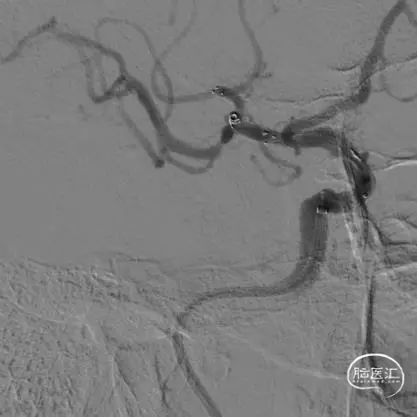

术后影像

术后即刻正侧位造影示:动脉瘤内无造影剂滞留,Raymond分级:3A级。